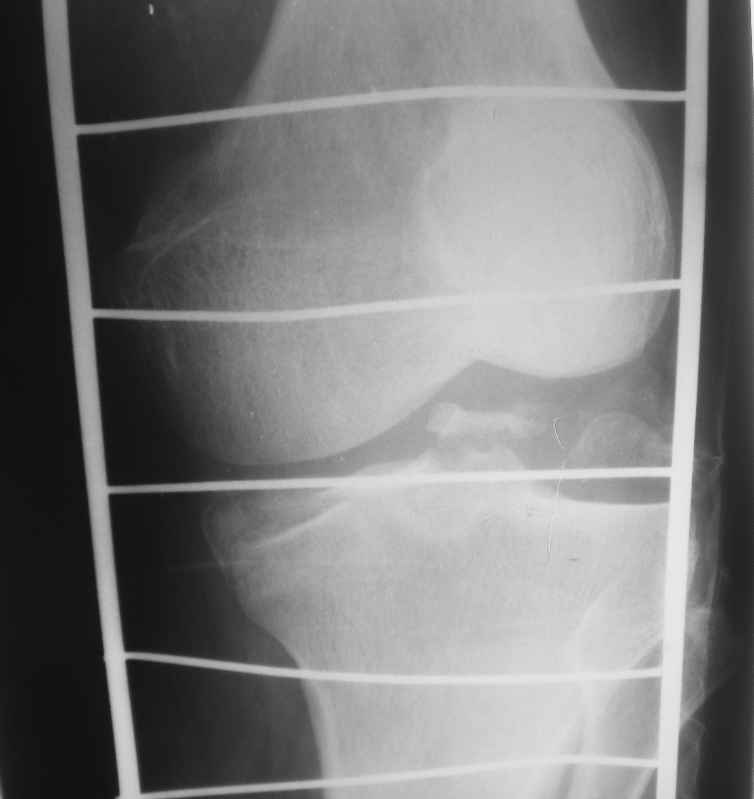

Re: Помогите определиться - перелом мыщелков правой большеберцовой кости

Высылаю рентгенограммы